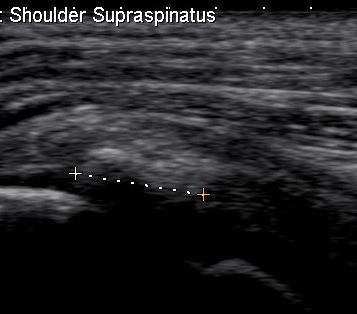

Ultrasound

Ultrasound Calcific TendonitisUltrasound Calcium Supraspinatous